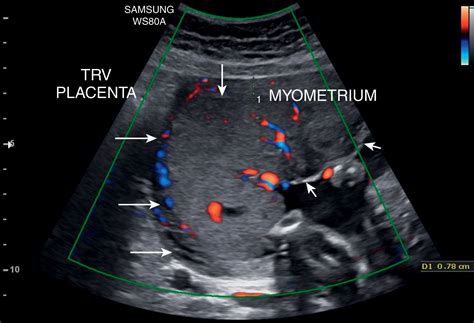

Placenta Accreta

Placenta accreta is a condition in which the placenta attaches too deeply into the uterine wall. This can cause severe bleeding during delivery and may require a hysterectomy. There are three types of placenta accreta:

• Placenta accreta: The placenta attaches to the myometrium (the muscular layer of the uterus).

• Placenta increta: The placenta invades the myometrium.

• Placenta percreta: The placenta invades through the myometrium and may attach to nearby organs, such as the bladder.

Diagnosing Placental Position

The placement of placenta is typically diagnosed during routine ultrasound examinations. Ultrasounds can provide detailed images of the uterus and placenta, allowing healthcare providers to determine the position of the placenta and assess any potential risks. Ultrasounds are usually performed during the second trimester, around 18 to 22 weeks of pregnancy, but may be repeated if there are concerns about the placenta’s position.